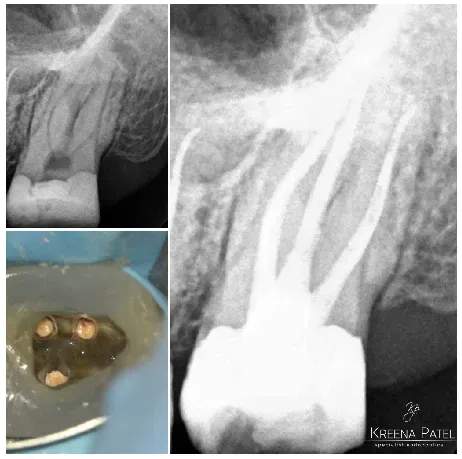

Máy định vị đỉnh cũng đặc biệt hữu ích để chẩn đoán thủng, gãy chân răng theo chiều ngang và tiêu xương. Máy định vị đỉnh sẽ đạt đến số đọc bằng không ngay khi giũa tiếp xúc với mô nha chu.

9.2. Đọc số không

Đọc số không là phép đo chính xác duy nhất được tạo ra bởi máy định vị chóp. Kiểm tra xem đọc có ổn định và di chuyển cùng với các chuyển động của dũa hay không.